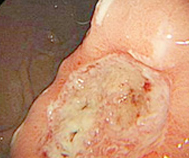

在郑州益好医院治愈的萎缩性胃炎患者

第一次检查萎缩性胃炎发生 病变、胃粘膜受损

第二次复查萎缩性胃炎中度

第三次复查完全康复